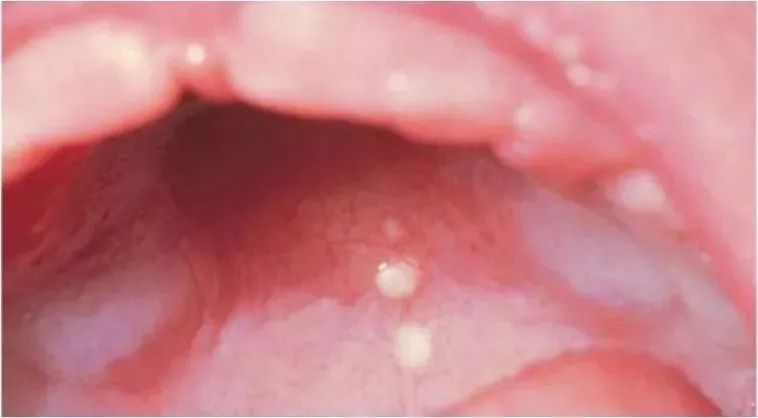

口腔內(nèi)有白點(diǎn)(馬牙、上皮珠)

在新生寶寶口腔的上腭中線附近會(huì)看到針頭或米粒大小的灰白色小點(diǎn),叫上皮珠,上皮珠是細(xì)胞脫落不完全所致。

在寶寶牙齒牙齦邊緣也會(huì)有白色小珠或灰白色硬塊,看起來好像萌出的牙齒,俗稱“板牙”或“馬牙”。

上皮珠和馬牙對寶寶沒有不良影響,不必做處理,會(huì)自然消失哦~